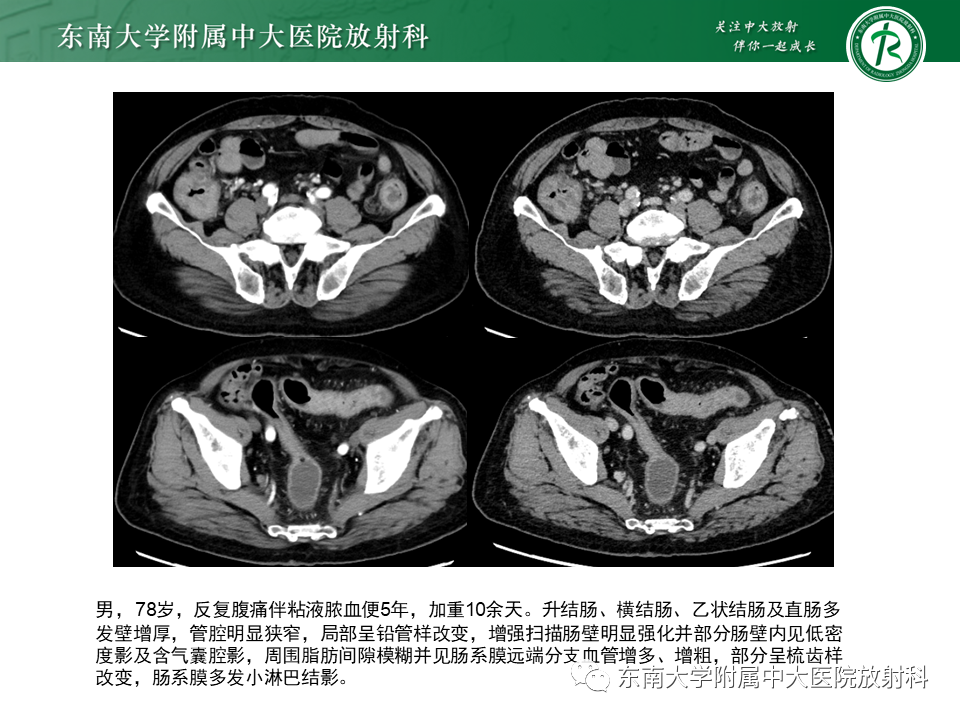

•患者1年前无明显诱因下出现腹痛,主要位于脐周,呈阵发性发作,未予重视。1年来症状时有发作,约1-2次/周,未正规就诊治疗。1月前患者自觉腹痛加重,伴有大便次数增多,约3次/日,稀糊状。外院胸腹部CT:1、胸部平扫未见异常;2、升结肠及部分横结肠管壁增厚,考虑克罗恩病可能,建议肠镜检查。彩超:肝胆胰脾未见异常。予以“甲泼尼龙、奥硝唑、头孢”等治疗5天,后腹痛症状有所缓解